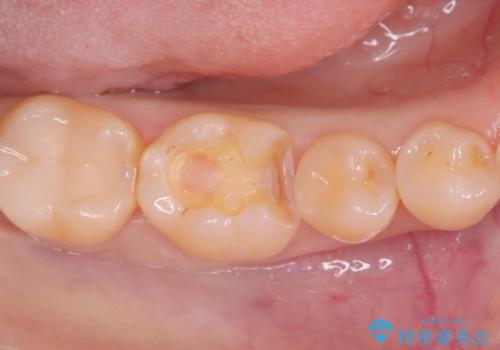

奥歯の銀歯を自然に!右下6番のメタルフリー治療

- 右下6番の奥歯に入っている金属の詰め物(メタルインレー)を気にされてご来院されました。お口の中の金属をなくしたいという患者様のご希望と、見た目の改善を目指し、天然歯に近い色と質感を持つセラミックインレーに交換する治療計画を立案しました。これにより、審美性の向上と、金属アレルギーのリスクがないメタルフリーの環境を実現することを目指しました。

治療では、まず古い金属のインレーを慎重に取り外し、内部に虫歯の再発がないかを丁寧に確認しました。歯を最小限だけ形成した後、精密な型取りから患者様の歯の色に合わせたオーダーメイドのセラミックインレーを作製しました。セラミックは、歯質との適合性が高く、プラークが付着しにくいため、虫歯の再発リスクを抑えるメリットもあります。適合性の高いセラミックインレーを装着することで、長年のコンプレックスだった銀歯がなくなり、機能的にも安定した自然な奥歯を取り戻していただけました。